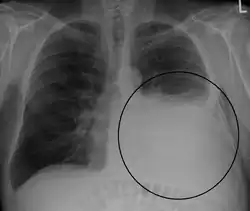

A pleural effusion appears as an area of whiteness on a standard posteroanterior chest X-ray.[15] Normally, the space between the visceral pleura and the parietal pleura cannot be seen. A pleural effusion infiltrates the space between these layers. Because the pleural effusion has a density similar to water, it can be seen on radiographs. Since the effusion has greater density than the rest of the lung, it gravitates towards the lower portions of the pleural cavity. The pleural effusion behaves according to basic fluid dynamics, conforming to the shape of pleural space, which is determined by the lung and chest wall. If the pleural space contains both air and fluid, then an air-fluid level that is horizontal will be present, instead of conforming to the lung space.[16] Chest radiographs in the lateral decubitus position (with the patient lying on the side of the pleural effusion) are more sensitive and can detect as little as 50 mL of fluid. Between 250 and 600mL of fluid must be present before upright chest X-rays can detect a pleural effusion (e.g., blunted costophrenic angles).[17]

- Massive left-sided pleural effusion (whiteness) in a patient presenting with lung cancer.